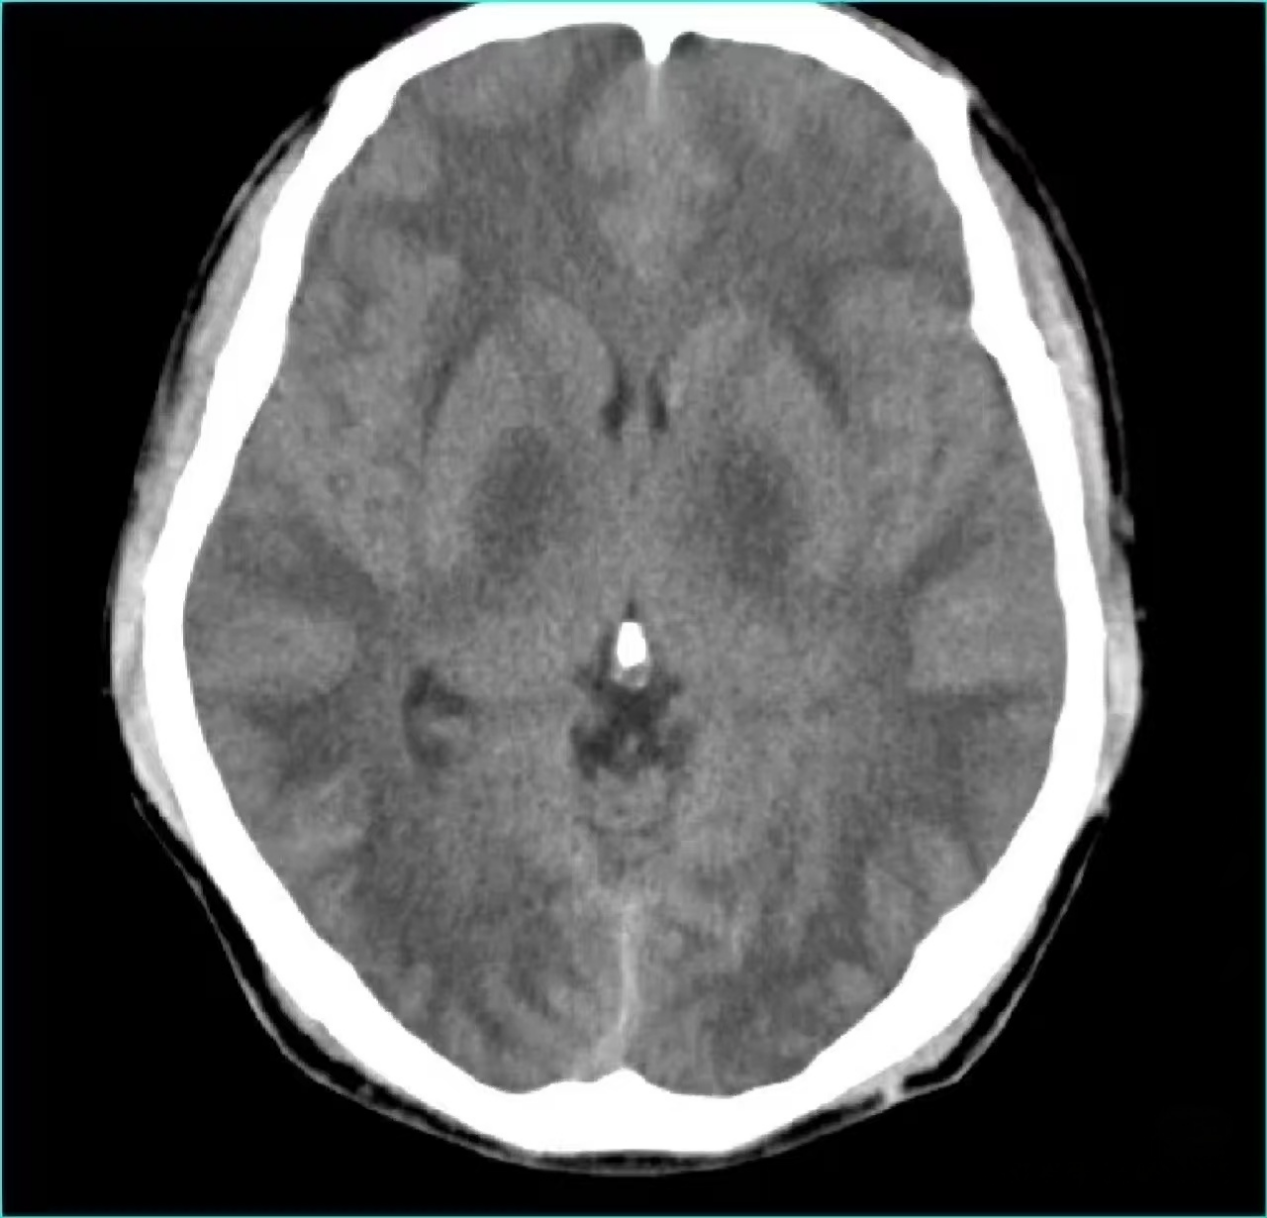

典型表现:病灶数量多、呈椭圆形,且垂直于大脑侧脑室分布(图1),或出现大片融合的异常信号(图2)。

图2